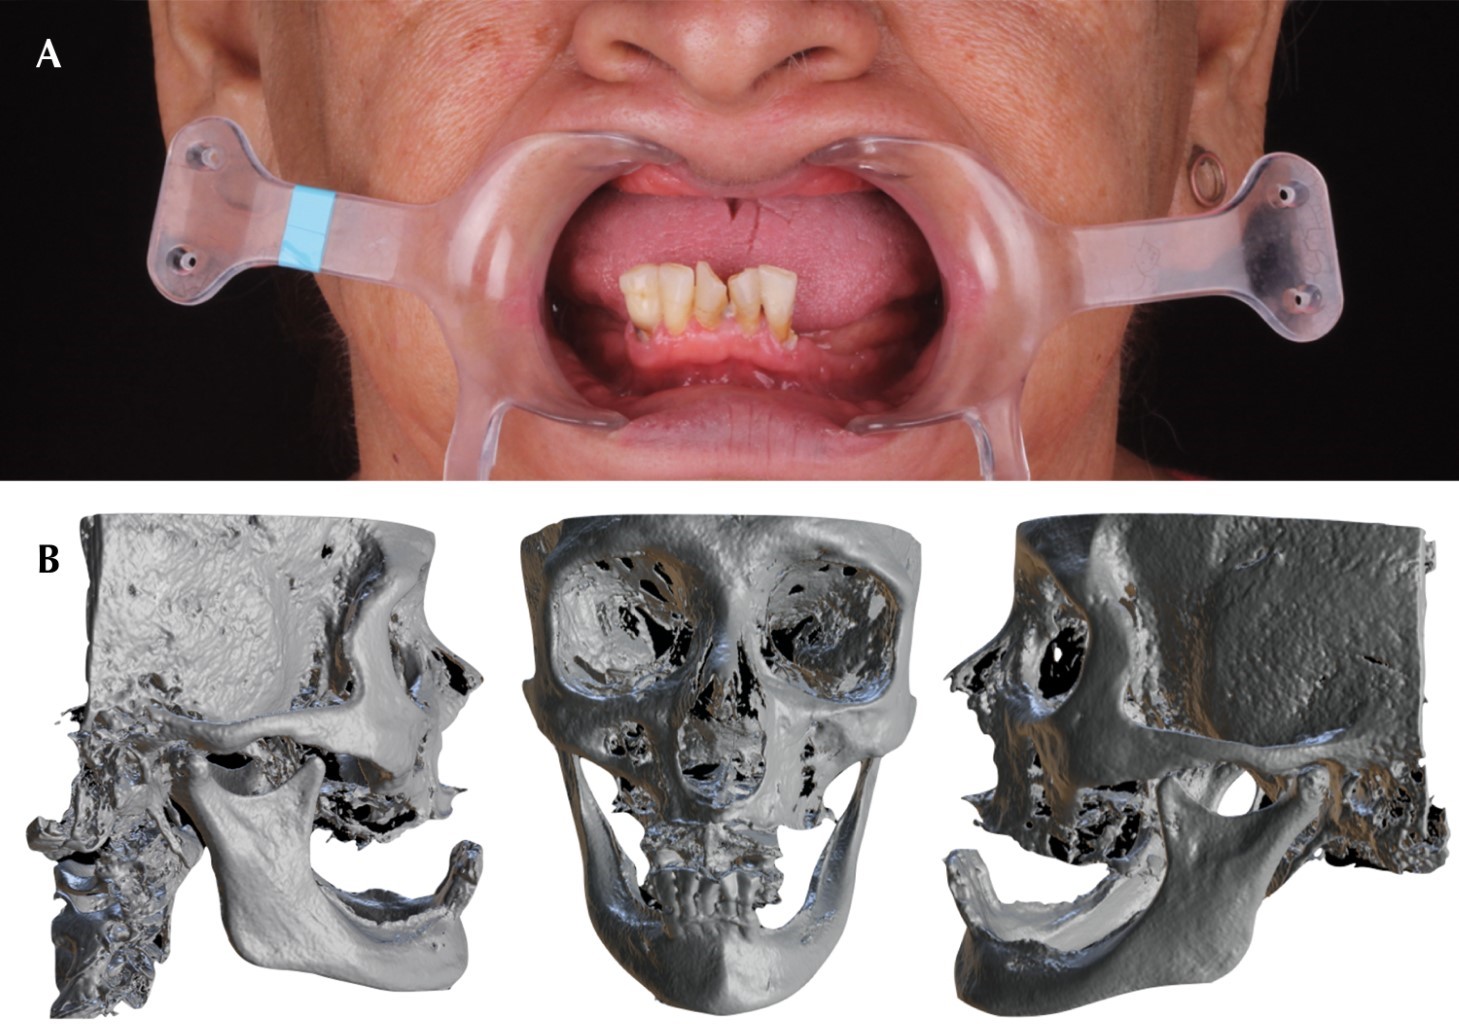

Vestibuloplasty with Er,Cr:YSGG laser and EPX biomolecule nanocarrier: a new periodontal healing agent.

Alveolar bone resorption often results in mucosal insertions interfering with the construction, stability and retention of a removable prosthesis, an option to modify this tissue is obtained by means of vestibuloplasty. Currently, wound healing can be promoted by using high power laser applied to oral surgical procedures. A case report of a female patient who underwent a vestibuloplasty procedure with laser Er,Cr:YSGG, using chitosan gel with EPX biomolecule nanocarriers postoperatively. A fast and favorable healing is observed when combining both therapeutics, besides, when using products with chitosan, the risk of necrosis of human gingival fibroblasts is reduced, as recently reported in the use of chlorhexidine mouthwashes.

Figure 1